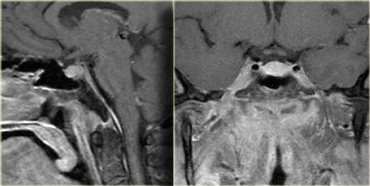

Schwannoma in CPA-region with typical features of an extraaxial tumor (T2WI) Schwannoma in CPA-region with typical features of an extraaxial tumor (T2WI)

The T2W-images show a schwannoma located in the cerebellopontine angle (CPA).

This case nicely demonstrates the typical signs of an extra-axial tumor.

There is a CSF cleft (yellow arrow).

The subarachnoid vessels that run on the surface of the brain are displaced by the lesion (blue arrow).

There is gray matter between the lesion and the white matter (curved red arrow).

The subarachnoid space is widened because growth of an extra-axial lesion tends to push away the brain.

All these signs indicate that this is a typical extra-axial tumor.

In the region of the CPA 90% of the extra-axial tumors are schwannomas.